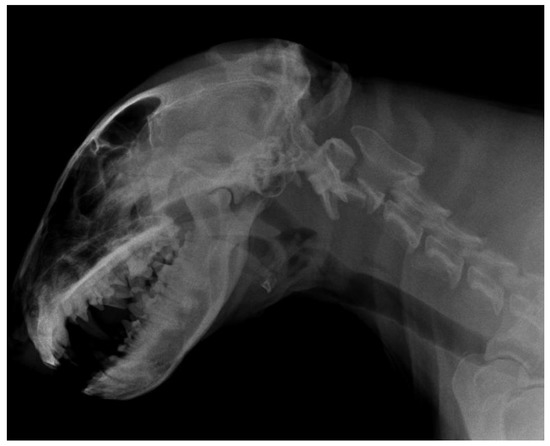

3.2. Diagnostic Imaging